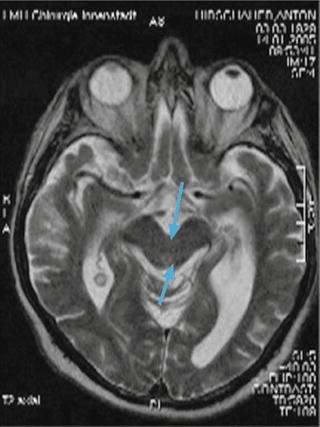

Globale Kortikale Atrophie